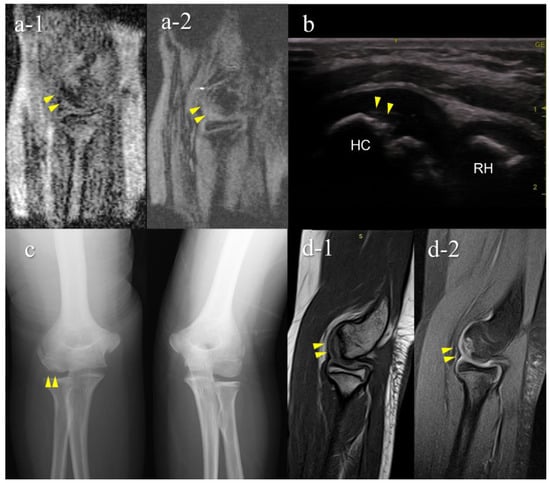

Figure 8. A very early stage of an OCD case (Case 7): Mobile MRI (+), US (−). (a) Mobile MR image of sagittal T1WI: Mobile MRI showing signal intensity changes reflecting bone marrow edema in the anterior humeral capitellum; (b) US image of the posterior longitudinal view: US did not show subchondral bone irregularity; (c) X-p AP view with elbow 45° flexed: X-p 45° showing a translucent area in the central capitellum, stage-I OCD; (d) 3T MR images: d-1, PDWI-FS sagittal image; d-2, PDWI coronal image: localization of the lesion was consistent with that of 3T MRI and mobile MRI.